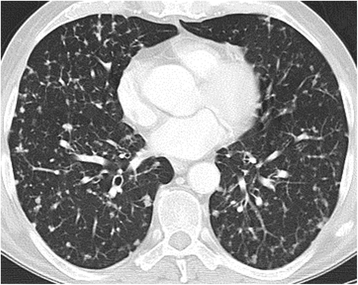

It includes hypersensitivity pneumonitis, interstitial pneumonitis with a pattern of non-specific interstitial pneumonia (NSIP) (Fig. 2), cryptogenic organizing pneumonia (COP), pulmonary haemorrhage, pulmonary oedema, bronchiolitis, vasculitis and many others.

A predominant reticular pattern with a basal and peripheral distribution in combination with ground glass is found in drug-induced lung disease with a NSIP pattern (non specific interstitial pneumonia).